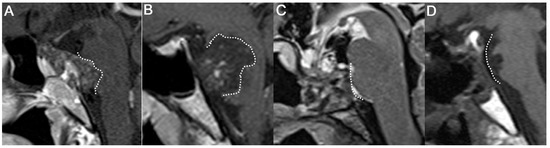

2.2. Surgical Strategy

2.3. Endonasal Transclival Approach